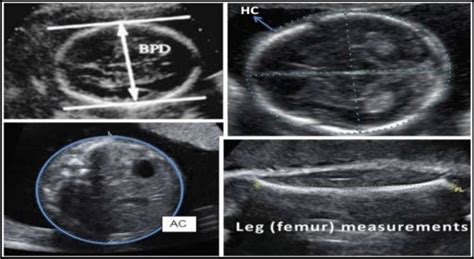

Understanding fetal development is crucial for monitoring a baby’s health during pregnancy. This article focuses on the normal ranges for key measurements like Biparietal Diameter (BPD), Head Circumference (HC), Abdominal Circumference (AC), and Femur Length (FL) at 30 weeks of gestation. These measurements, obtained through ultrasound, provide valuable insights into the baby’s growth and well-being. Let’s dive into what these measurements mean and what ranges are considered normal at this stage of pregnancy.

At 30 weeks, your baby is going through significant development, and ultrasounds play a vital role in assessing their growth. The measurements taken during these scans, including BPD (Biparietal Diameter), HC (Head Circumference), AC (Abdominal Circumference), and FL (Femur Length) , are key indicators of fetal health. Understanding these measurements helps healthcare providers ensure that your baby is developing as expected. Let’s break down each of these measurements and their significance.

The Biparietal Diameter (BPD) measures the distance between the two sides of the baby’s head. This measurement is taken from one parietal bone to the other and is an important indicator of head growth. At 30 weeks, the normal range for BPD typically falls between 71 and 85 millimeters. This measurement helps doctors assess the baby’s overall growth and development, especially in relation to the head. If the BPD is outside this range, it doesn’t automatically mean there’s a problem, but it warrants further investigation to rule out any potential issues. Factors such as genetics, gestational age accuracy, and individual growth patterns can influence the BPD. Accurate BPD measurements are crucial for estimating gestational age and monitoring growth patterns throughout the pregnancy. Regular monitoring ensures that any deviations from the normal range are identified early and addressed appropriately, contributing to better prenatal care and outcomes.

Head Circumference (HC) measures the distance around the baby’s head. This measurement provides a more comprehensive assessment of head size compared to BPD alone. At 30 weeks, the normal range for HC is generally between 272 and 296 millimeters. HC is particularly useful because it is less affected by head shape variations than BPD. Monitoring HC helps healthcare providers assess brain growth and development. Significant deviations from the normal range can indicate potential issues such as microcephaly (smaller than normal head size) or hydrocephalus (excess fluid in the brain). However, it’s important to consider other factors and conduct further evaluations before making any definitive conclusions. Consistent and accurate HC measurements, combined with other fetal biometry data, provide a comprehensive view of the baby’s growth trajectory. This helps in identifying potential concerns early on, allowing for timely intervention and management to support optimal fetal development.

The Abdominal Circumference (AC) measures the distance around the baby’s abdomen. This measurement is a key indicator of the baby’s size and nutritional status. At 30 weeks, the normal range for AC typically falls between 245 and 283 millimeters. AC is closely related to the baby’s weight and is used to estimate fetal weight. It is also an important marker for assessing the baby’s overall health and growth. Significant deviations from the normal AC range can indicate potential problems such as intrauterine growth restriction (IUGR) or macrosomia (excessive fetal growth). IUGR can occur if the baby is not receiving enough nutrients, while macrosomia can be associated with gestational diabetes. Regular monitoring of AC, along with other fetal measurements, helps healthcare providers assess the baby’s growth pattern and identify any potential nutritional or metabolic issues. This allows for timely interventions such as dietary adjustments or closer monitoring to ensure the baby’s healthy development.

The Femur Length (FL) measures the length of the baby’s thigh bone. This measurement is used to assess the baby’s skeletal growth. At 30 weeks, the normal range for FL is generally between 54 and 60 millimeters. FL is an important indicator of overall bone development and can help estimate gestational age, particularly in the second trimester. Significant deviations from the normal FL range may indicate skeletal dysplasia or other bone growth abnormalities. However, it’s important to consider other factors and conduct further evaluations before making any definitive conclusions. Genetic factors and individual growth patterns can also influence FL. Accurate FL measurements, combined with other fetal biometry data, provide a comprehensive view of the baby’s skeletal development. This helps in identifying potential concerns early on, allowing for timely intervention and management to support optimal fetal growth.